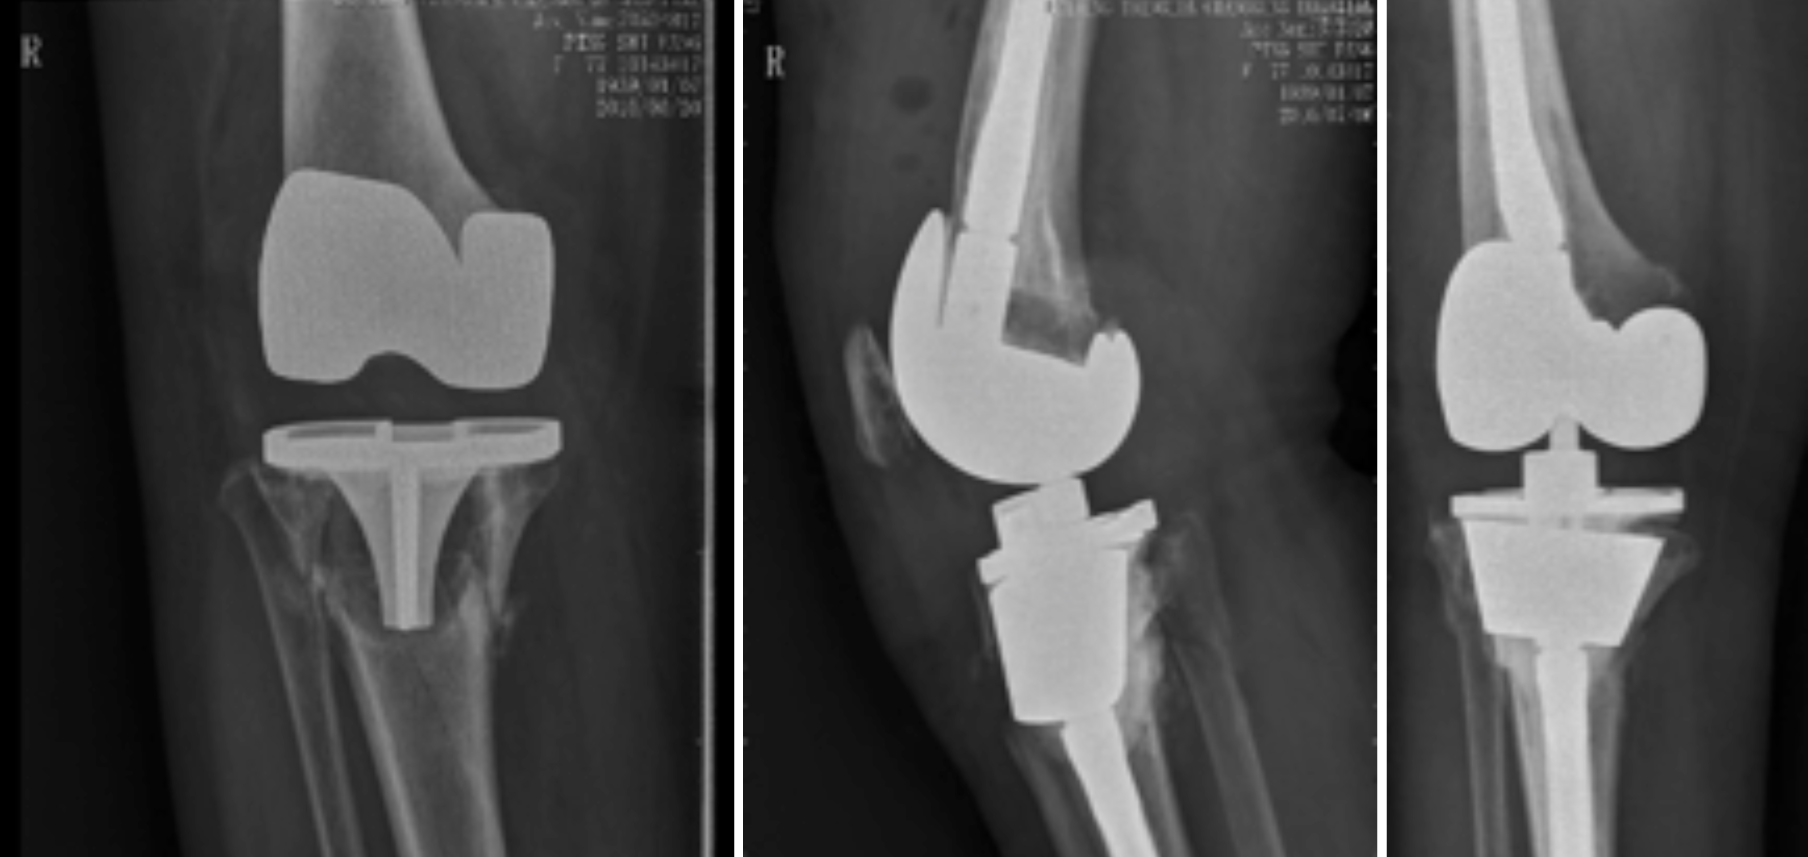

一、人工关节置换 各种晚期骨关节病的关节置换手术治疗是北京清华长庚医院关节外科中心的一大特色,包括股骨头坏死、髋膝骨关节炎、类风湿关节炎、强直性脊柱炎、髋关节发育不良、关节强直、超过80岁的超高龄股骨颈骨折患者的关节置换手术等,我中心在人工关节初次置换及翻修上作了大量工作,置换的难度和手术效果方面已达到国际先进水平,导航下全膝关节置换术:大大提高膝关节置换手术的精确度。

局限性关节置换手术(UKA)

全膝关节表面置换手术(TKA)

铰链式人工膝关节置换手术(HK)膝关节周围韧带严重破坏

国内首例膝关节置换术后Felix IIB型胫骨假体周围骨折翻修术